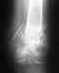

Re: Кость так и не срастается

Покупать еще один стержень нет денег. За один отдал 25т.р. Ходить в аппарате больше не хочу - из дому невозможно выйти, сами понимаете. И так 4 месяца провел в 4 стенах. В гипсе хотя бы могу ходить и водить машину одной рукой.

Пластина тоже денег стоит не малых, хоть и дешевле. Но мне она вряд ли подойдет, так как худая рука.

А почему вы не даже рассматриваете вариант установки дополнительного шурупа в ту часть кости, которая не закреплена? В конце стержня нет технологических отверстий, но есть пазы. То есть короткий не сквозной шуруп, который упрется в стержень и придавит его (держась резьбой за стенку кости) к другой стенке кости. А попав в паз на стержне, еще ограничится и хождение кости вдоль стержня.